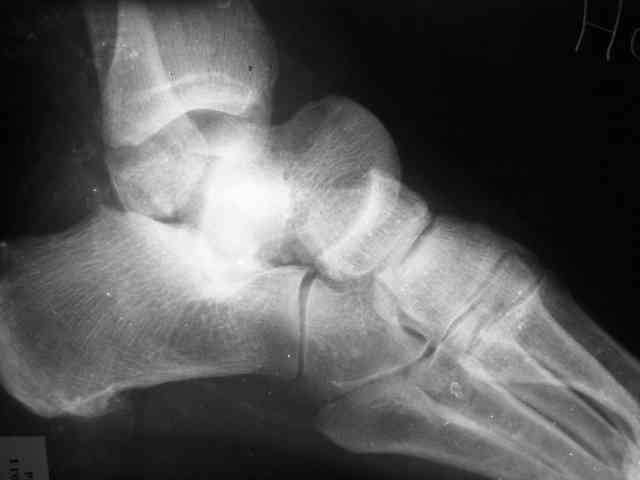

Уважаемый Александр! Как обещал представляю Р-граммы и операционные фото.

Последний снимок

Мнение по поводу тарана? АН есть?

> Мнение по поводу тарана? АН есть?

Типичная картина некроза.